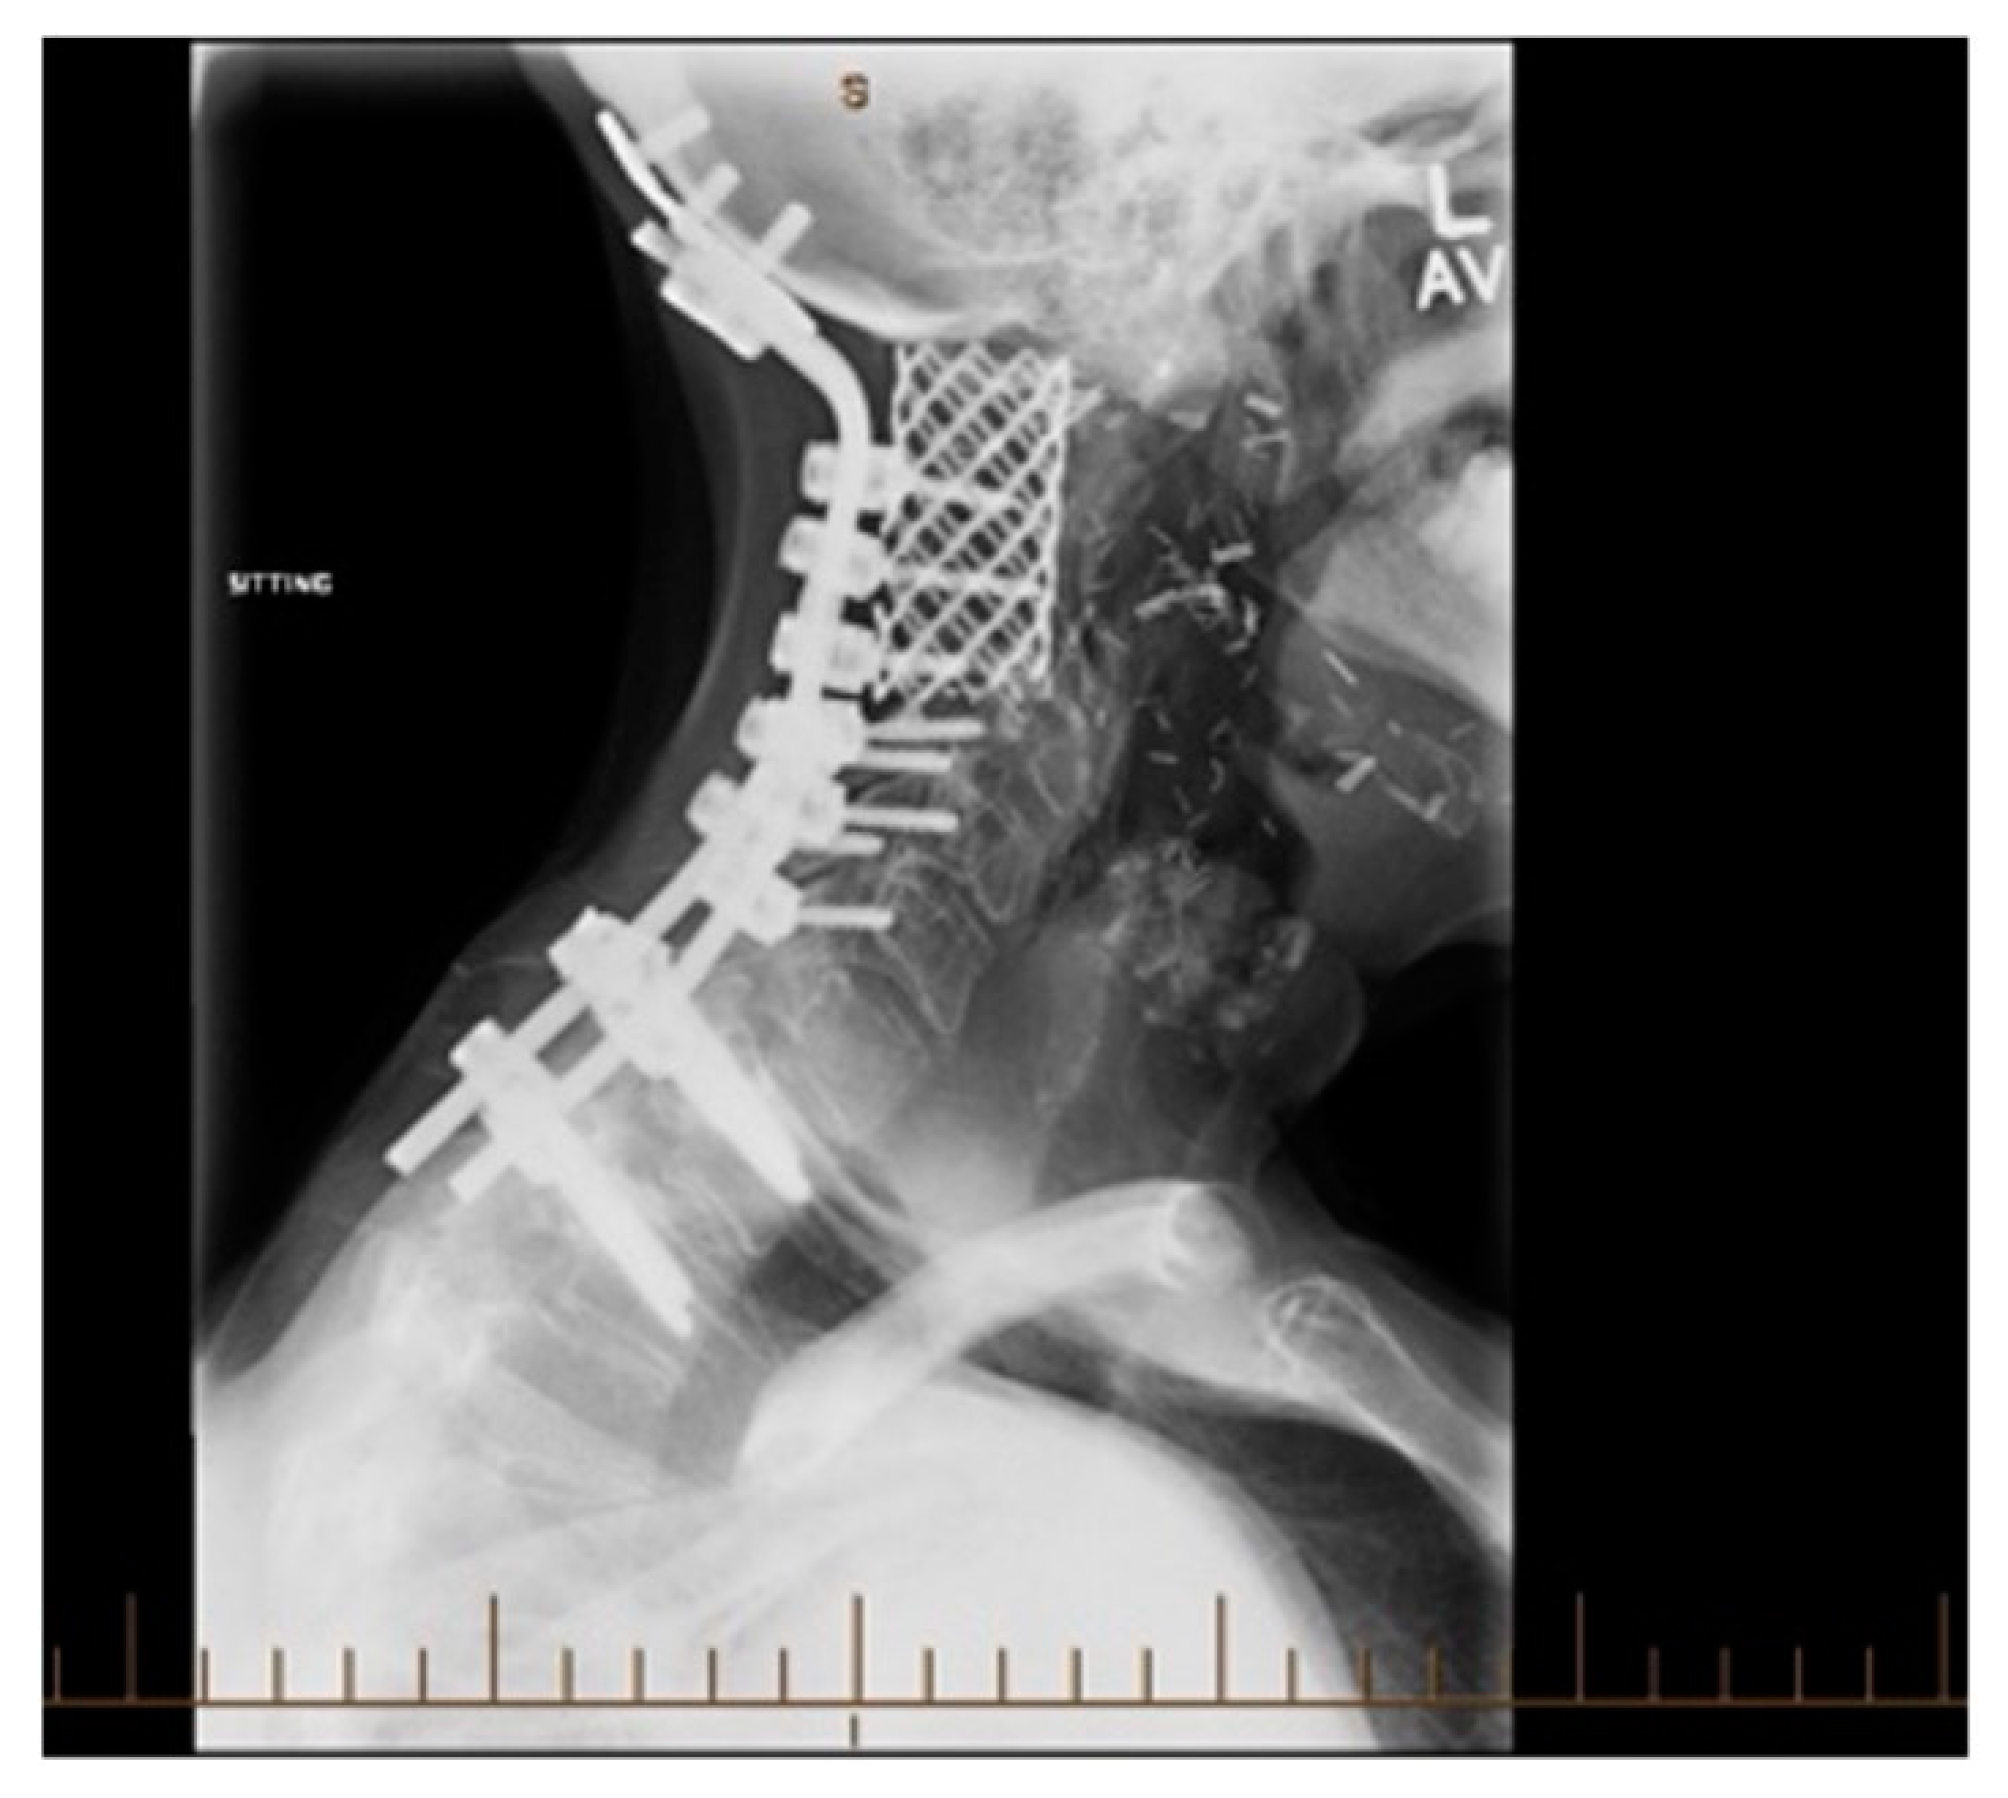

3.1.4. Outcomes

3.2.3. Treatment

3.2.4. Outcomes